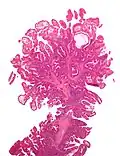

| Ворсинчатая аденома | Пальцеобразные выступы, вытянутые от поверхности полипа с минимальным ответвлением, незначительная дисплазия с потерей муцина, удлиненные ядра с гиперхроматизмом.[6] | Да | ![]() |

|